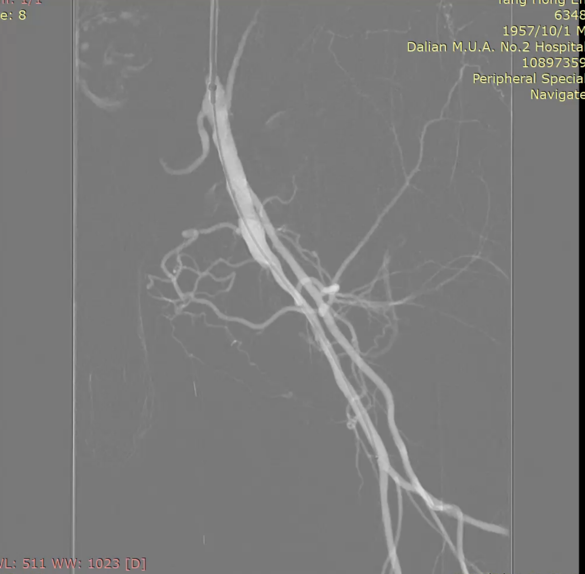

★ case2 股深单一流出道 ——SFA闭塞导致髂支架血栓

Roterax+ CDT一日

覆膜支架肾下对吻

6个月后

左侧支架血栓形成